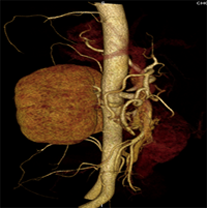

同一病人利用容積數據進行三維處理后,高品質MPR和三維圖像上則清晰顯示了縱向排列的腹腔干與腸系膜上動脈相鄰近,血管發生變 異,近端血管閉塞,為臨床提供了精確的診斷信息。

從上面的例子可以看到,能否為臨床提供高品質的三維影像成為了16層CT的核心價值,而東芝新一代的 全景三維16層CT擁有最為 先進的3項核心技術,在16層核心價值上的表現自然值得期待。